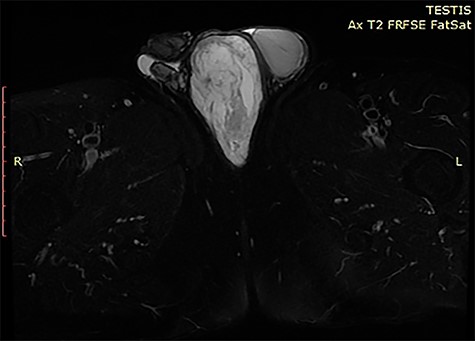

A 57-year old male presented to surgery outpatient clinic of the hospital with scrotal mass. His initial review of systems was negative for any complaints except a feeling of heaviness at the scrotum. On clinical examination, the mass was mobile and did not transilluminate. The lesion had gradually increased in size during the last 2 years. The overlying skin was normal. The patient’s medical history like his family was normal. Ultrasound revealed a weak and heterogeneous echogenic mass (Fig. 1), and after the imaging with computed tomography (CT) and magnetic resonance imaging (MRI) (Figs 2 and 3) of the pelvis, we proposed surgical excision of the mass. Preoperatively, there was no suspicion of the diagnosis of aggressive angiomyxoma. Moreover, the differential diagnosis was between lipoma and testicular malignances. We preferred a perineal procedure with patient in lithotomy position; also the team was composed of a general surgeon and an urologist. We extracted a mucoid mass en bloc with free macroscopic margins. The mass was 11 cm in its max diameter, this was extended to the pubic symphysis and displaced the urethra without infiltrated it. The histological examination revealed small spindle-shaped cells without atypia or mitosis proliferating in an edematous to fibrous stroma and numerous small- to medium-sized thick-walled vessels. Around the mass was a smooth muscle integument. The neoplasmatic cells had the expression of desmin, CD34, S100, vimentin, smooth muscle antibody, estrogen receptor 40%, progesteron receptor 20% and Ki67-5%. Postoperatively, our patient had an uneventful recovery. A postoperative SPECT was negative for metastatic disease, and the 2-year follow-up is negative for recurrence of the disease.

Aggressive angiomyxoma is a rare entity most frequently between reproductive age women (male/female: 1/7) [3]. Aggressive angiomyxoma or deep angiomyxoma as referred by the world health organization is a mesenchymal malignancy first described in 1983 by Steeper and Rosai. This tumor most commonly derived from the female vulvar region, pelvis and perineum and male scrotum and inguinal region, but there are a few cases with non-pelvic invasion [4, 5]. At the most cases, angiomyxoma is an asymptomatic gradually enlargement mass, the symptoms in most patients are swelling without pain, abdominal distention, hematuria or vaginal hemorrhage in women. In our case, the only symptom was the palpable mass of the scrotum [1, 6]. The differential diagnosis of the palpable mass of scrotum in men patients is between perineal cyst, inguinal hernia, hydrocele, lipoma, abscess, leiomyoma, leiomyosarcoma, liposarcoma, testicular tumors or unidentified masses. The examination of the mass should begin with ultrasound tomography, which demonstrates a hypoechoic, well-demarcated mass with multiple thin echogenic internal septa, and for more detailed imaging, we can use computed tomography or magnetic resonance imaging, which on T2 weighted image has high signal intensities, or digital subtraction angiography to recognize the details of mass structure, to identify the relations between the near anatomical structures in order to organize the operation. Aggressive angiomyxoma has a distinctive imaging appearance of swirled or layered pattern in the tumor after enhancement on CT and MRI [7–9] with intravenous contrast injection. Preoperative diagnoses require high degree of suspicion. There are a few cases with preoperative histological diagnoses with CT assisted biopsy, but in most described cases the diagnosis was made postoperatively with the histological examination of the mass. Histologically, the typical findings include stellate to spindle-shaped tumor cells with fibromyxoid stroma and hyalinized thin-to-thick wall vessels and no necrosis or cystic changes, and the immunohistochemical studies show the expression of vimentin, smooth-muscle actin and CD34 to be strongly positive, the desmin, estrogen receptors and progestin receptors to be median positive, but mostly negative for S-100 and CD68 [3]. The more effective treatment for aggressive angiomyxoma is the radical free margin surgical excision. However, the risk of local recurrence is high especially within 2–3 years after the first operation. A reason for local recurrence is the incomplete surgical excision; however; Chan et al. [6] report no difference in recurrence in patients with negative margins compared with those with positive margins. In general, aggressive angiomyxoma has no tendency for distal metastases, but there was a report of a case with lung and mediastinum metastases. Radiation therapy has proposed as a monotherapy or as control of multiple recurrences after surgical excision, with poor results [10]. Chemotherapy has poor results in aggressive angiomyxoma because of the slow progress of the disease. Monotherapy may has a role in control of these tumors because of the expression of ER and PR receptors.